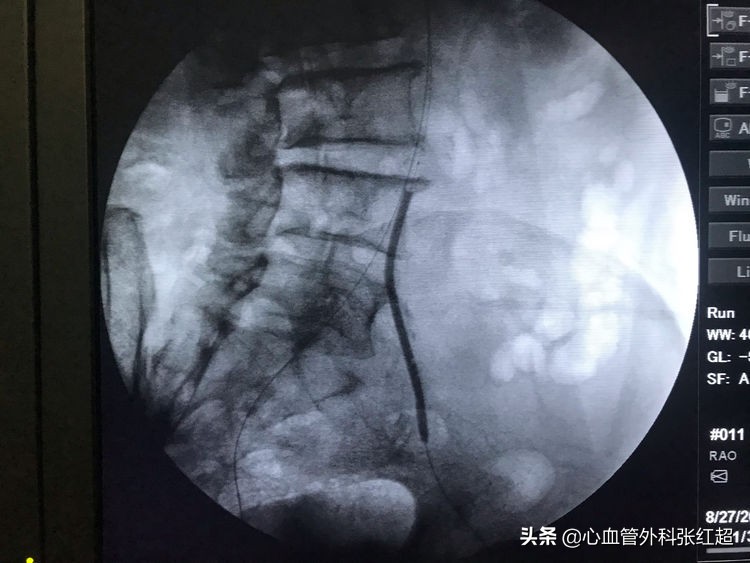

导丝进入假腔方向,加用微导管,换导丝破膜入真腔。

方位验证导丝入真腔后,用微导管造影进一步验证。

送入小球囊扩张,目的:①预防出血;②预防血栓脱落。

扩张时一定注意保持外鞘位置,避免血肿形成。

扩张中患者有痛应终止,防心弯曲部分球囊肩撕性撕裂。